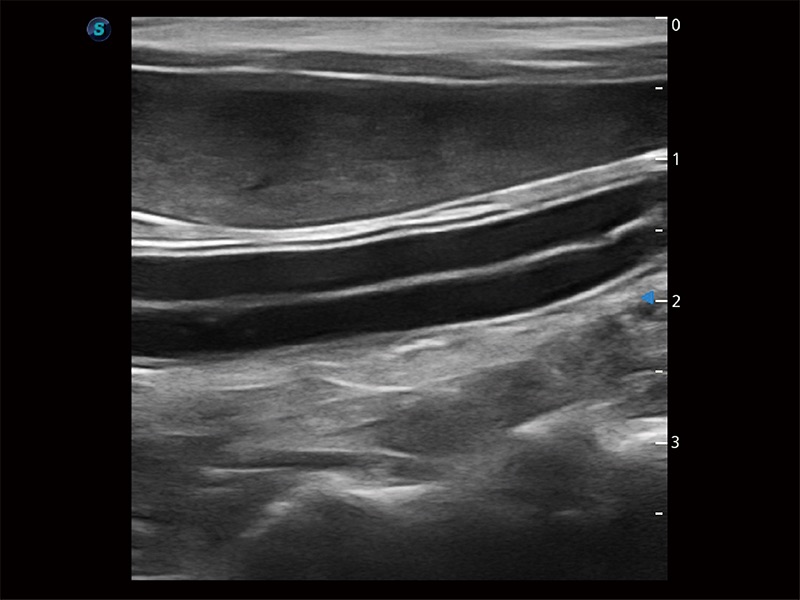

极大提升超低速微细血流的检出能力,同时更精准地滤除软组织和超声信号,为兽用医生提供以往无法通过常规血流获得的疾病诊断信息。

在传统二维血流成像的基础上,呈现血流的立体感,具有动感的生命力之美。即便是微小的血管也能轻松应对,提高了血流的视觉敏感性。

操作简便,无需高频度外力作用即可真实反映组织的形变,快速评估肿瘤良恶性。